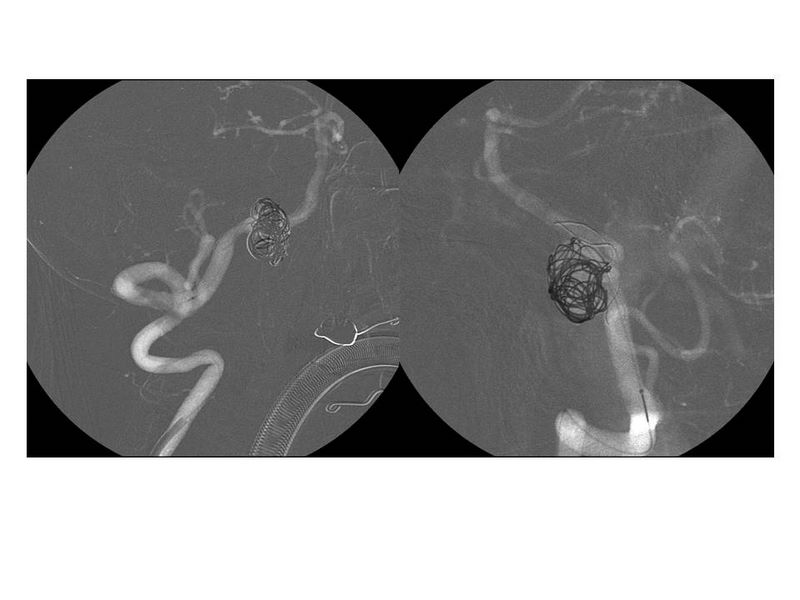

Aneurismas grandes